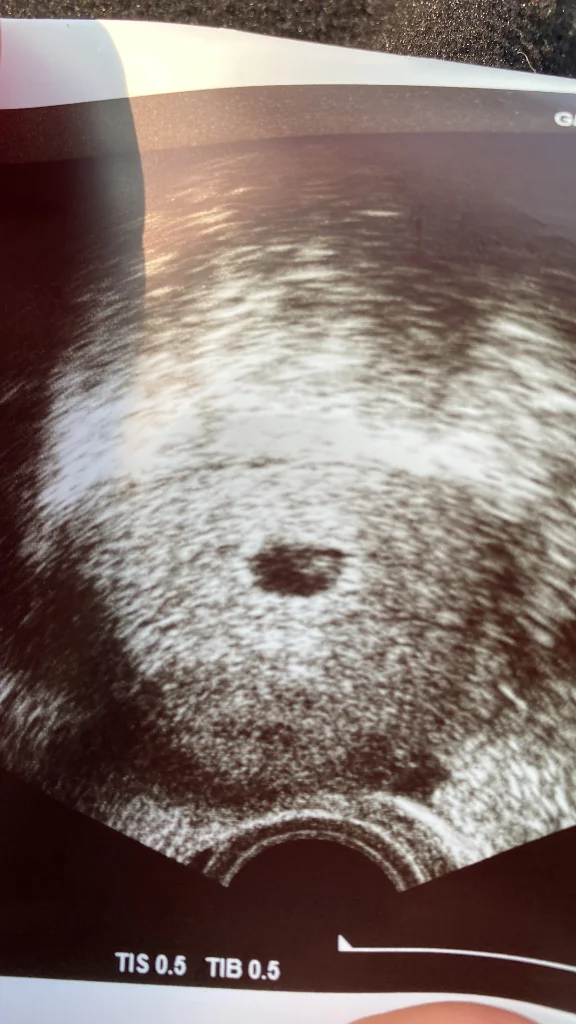

Maşallah canım. Kaçıncı hafta olmuş oluyo şimdi sizin.Kızlar buda benm keseem10 martta kalp atışı görücez inşallah

maşallah canım darısı başıma inşallah kaçıncı gün gördün keseyiKızlar buda benm keseem10 martta kalp atışı görücez inşallah

5. Haftadaym şuanmaşallah canım darısı başıma inşallah kaçıncı gün gördün keseyi